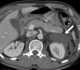

Splenic hematoma

A splenic injury, which includes a ruptured spleen, is any injury to the spleen. The rupture of a normal spleen can be caused by trauma, such as a traffic collision. [Source: Wikipedia ]